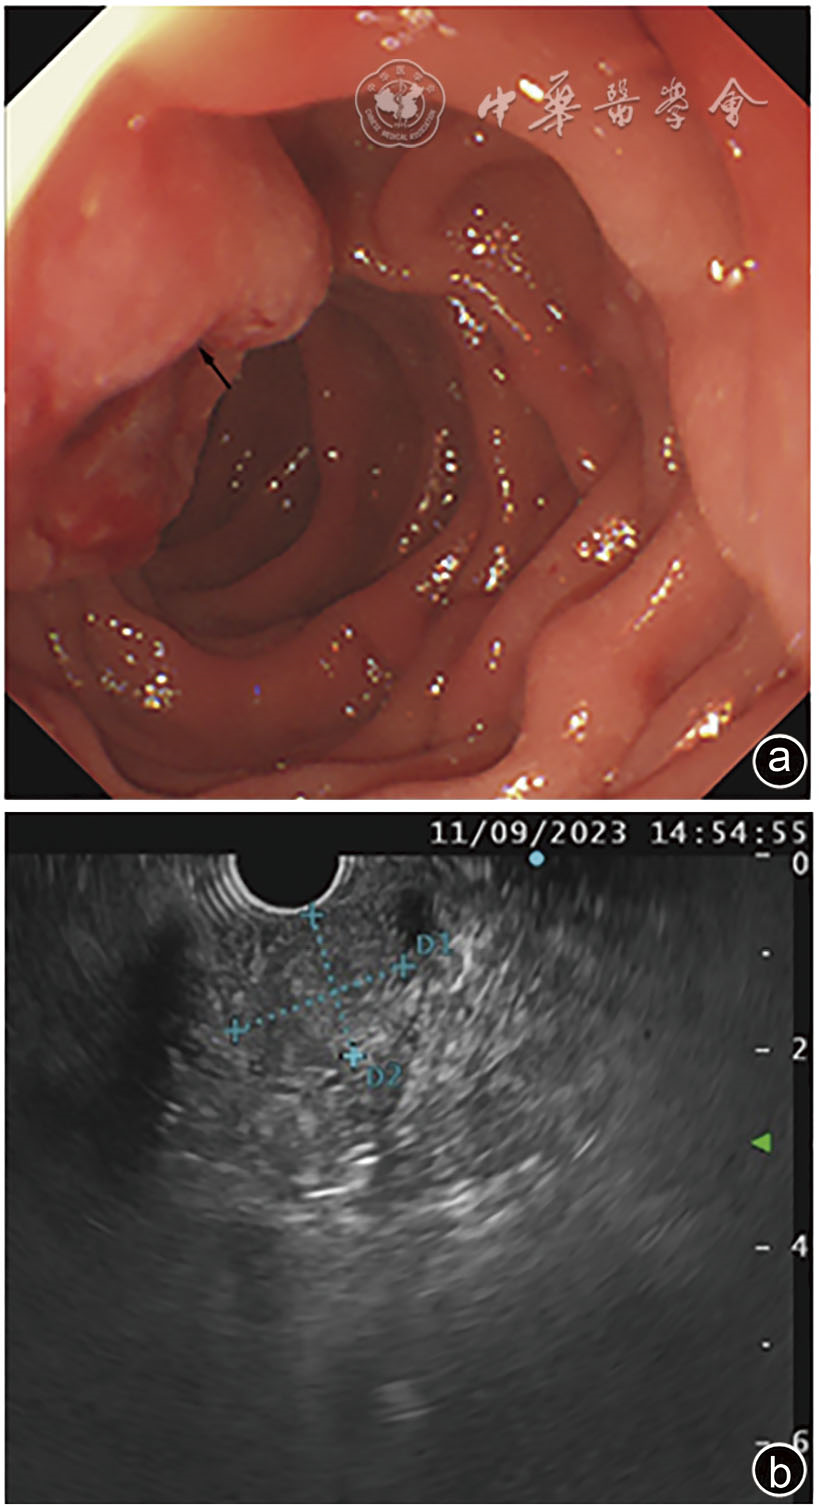

In this report, a 63-year-old male patient was admitted due to "dull pain in the right upper abdomen for 2 months". Imaging and pathological examination confirmed the diagnosis of synchronous hepatocellular carcinoma (CNLC Ⅰa stage) and duodenal papillary carcinoma (moderately-poorly differentiated adenocarcinoma complicated with signet ring cell carcinoma). The patient had a history of chronic hepatitis B. After Multidisciplinary team (MDT) consultation, laparoscopic local resection of segment 5 of the liver combined with pancreatoduodenectomy were performed to achieve R0 resection. Liver metastasis occurred 2 months after operation, and it was completely relieved after TACE, tirelizumab immunotherapy and FOLFOX4 chemotherapy. Postoperative survival time has exceeded 16 months. This case of synchronous double primary carcinoma of the liver and duodenal papilla is extremely rare, and it is likely to miss the diagnosis in clinical practice, suggesting that after the diagnosis of one type of malignant tumor, comprehensive evaluation is still needed to exclude other primary lesions. PET-CT shows important value in the early identification of such multiple primary cancers. Through multi-mode strategy of individualized comprehensive treatment and whole-course management, this patient achieved favorable tumor control effect, providing reference for clinical diagnosis and treatment of such rare cases.